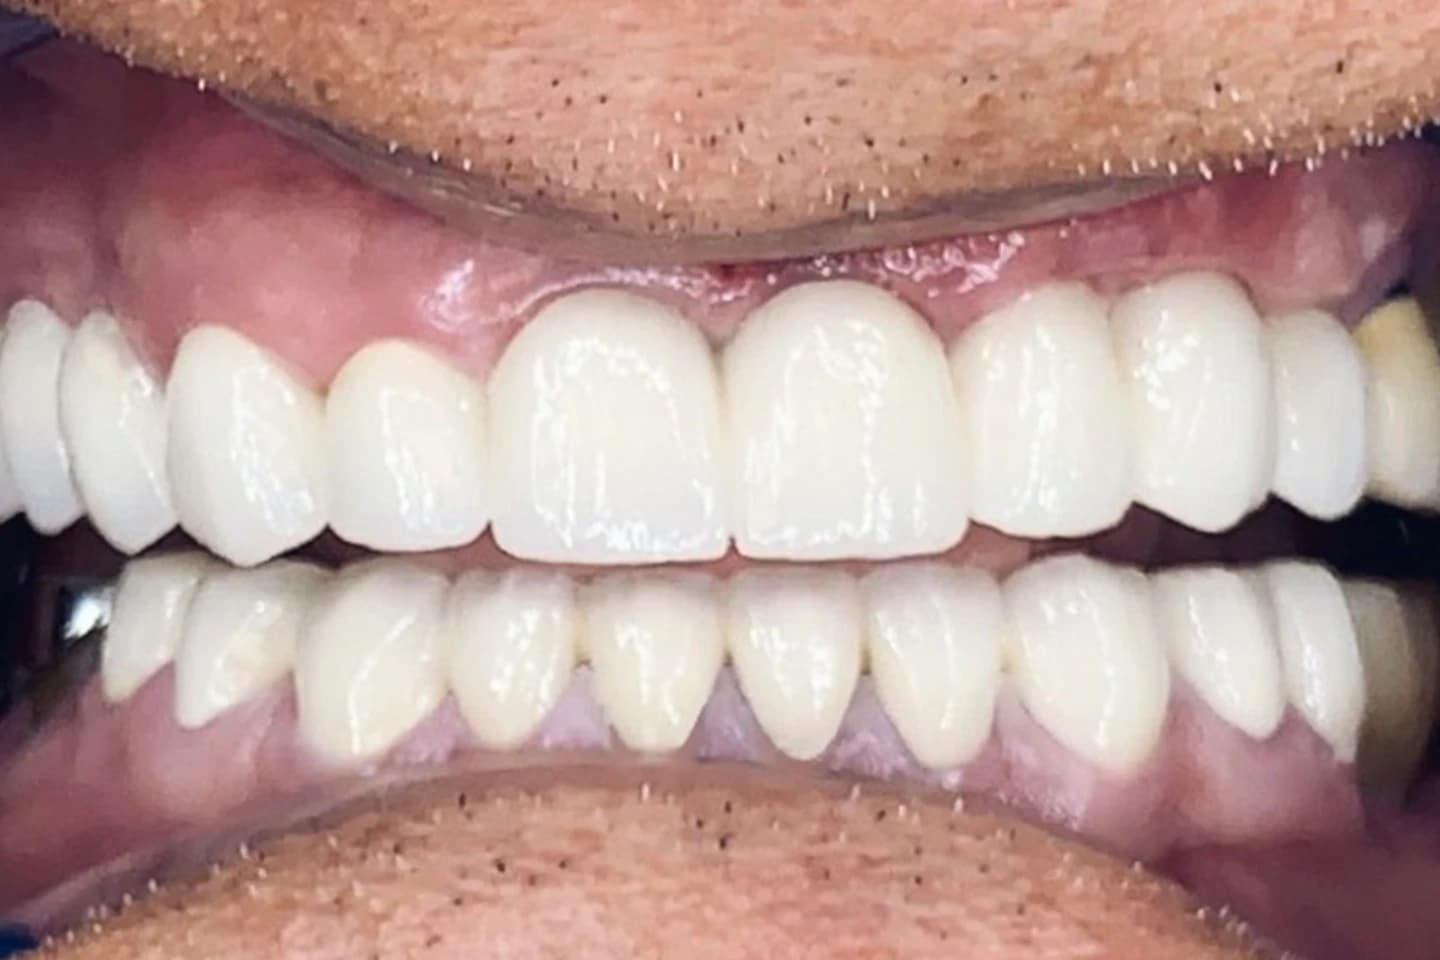

Krunice za zube - pre i posle

- Pogledajte kako krunice mogu da zaštite i obnove oštećenost kada su u pitanju zubi, vraćajući im estetiku i funkciju. Galerija radova će vas inspirisati da i vi transformišete svoj osmeh.